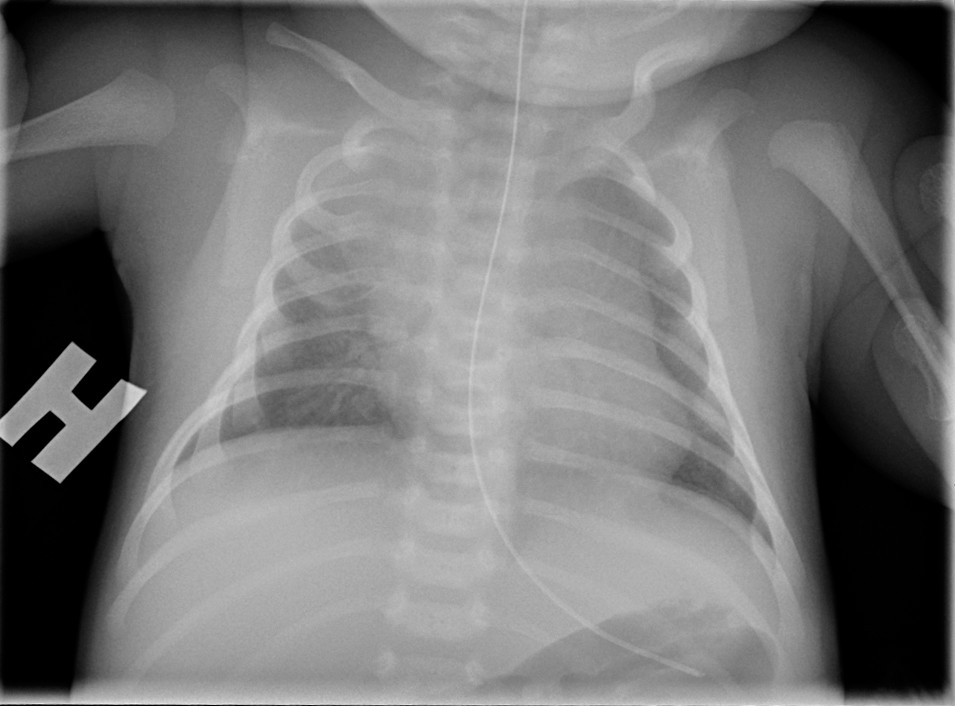

En 14-dager gammel lett prematur gutt ble innlagt grunnet redusert matinntak og mindre spontanbevegelse av høyre arm. Klinisk undersøkelse ga upåfallende funn, bortsett fra asymmetrisk spontanbevegelse av armene. C-reaktivt protein (CRP) var 29 mg/l (< 5 mg/l), og det var normale b-leukocytter. Røntgen thorax var upåfallende (bilde 1). Dagen etter innleggelsen ga MR mistanke om bløtvevsinfeksjon langs høyre thoraxvegg, og man startet med ampicillin og gentamycin intravenøst. Barnet hadde ikke feber. Senere på dagen steg CRP til 60 mg/l, og ultralyd av brystveggen viste høyresidig subkutan inflammasjon. Det var ingen synlige inflammasjonstegn i overliggende hud, men gutten var uttalt irritabel og smertepåvirket. Klindamycin ble da lagt til opprinnelig antibiotikaregime for å dekke for nekrotiserende fasciitt.